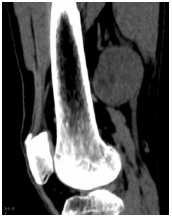

A left thigh CT examination (AQUILON GE VOLUSON 16 slice CT machine) showed a soft tissue attenuating lesion which was well-defined, ovoid and size measuring 5.9 x 4.8 x 5.6 cm in the posterior aspect of lower thigh. No intralesional calcifications were noted (Figure 4). There was no extension of the skin, subcutaneous plane, muscular plane and involvement of the bones. Contrast CT study showed homogenous enhancement (Figure 5).

Figure 4: CT showing soft tissue attenuating lesion in the posterior aspect of the lower thigh